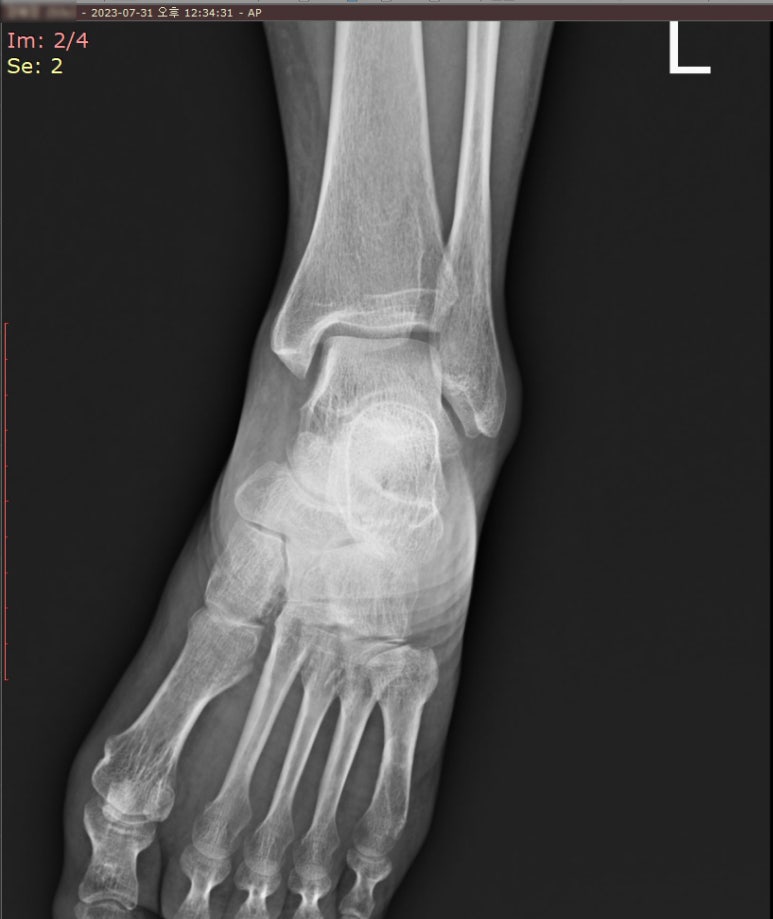

X-ray 검사에서 보이지 않는 발등 골절

정면과 측면에서 본 왼쪽 발등은

"left is not remarkable"

골절선이 보이지 않았습니다.

이러한 실금은 엑스레이에서 보이지 않을 수 있기 때문에 CT도 함께 의뢰했는데, CT에서는 어땠을까요?